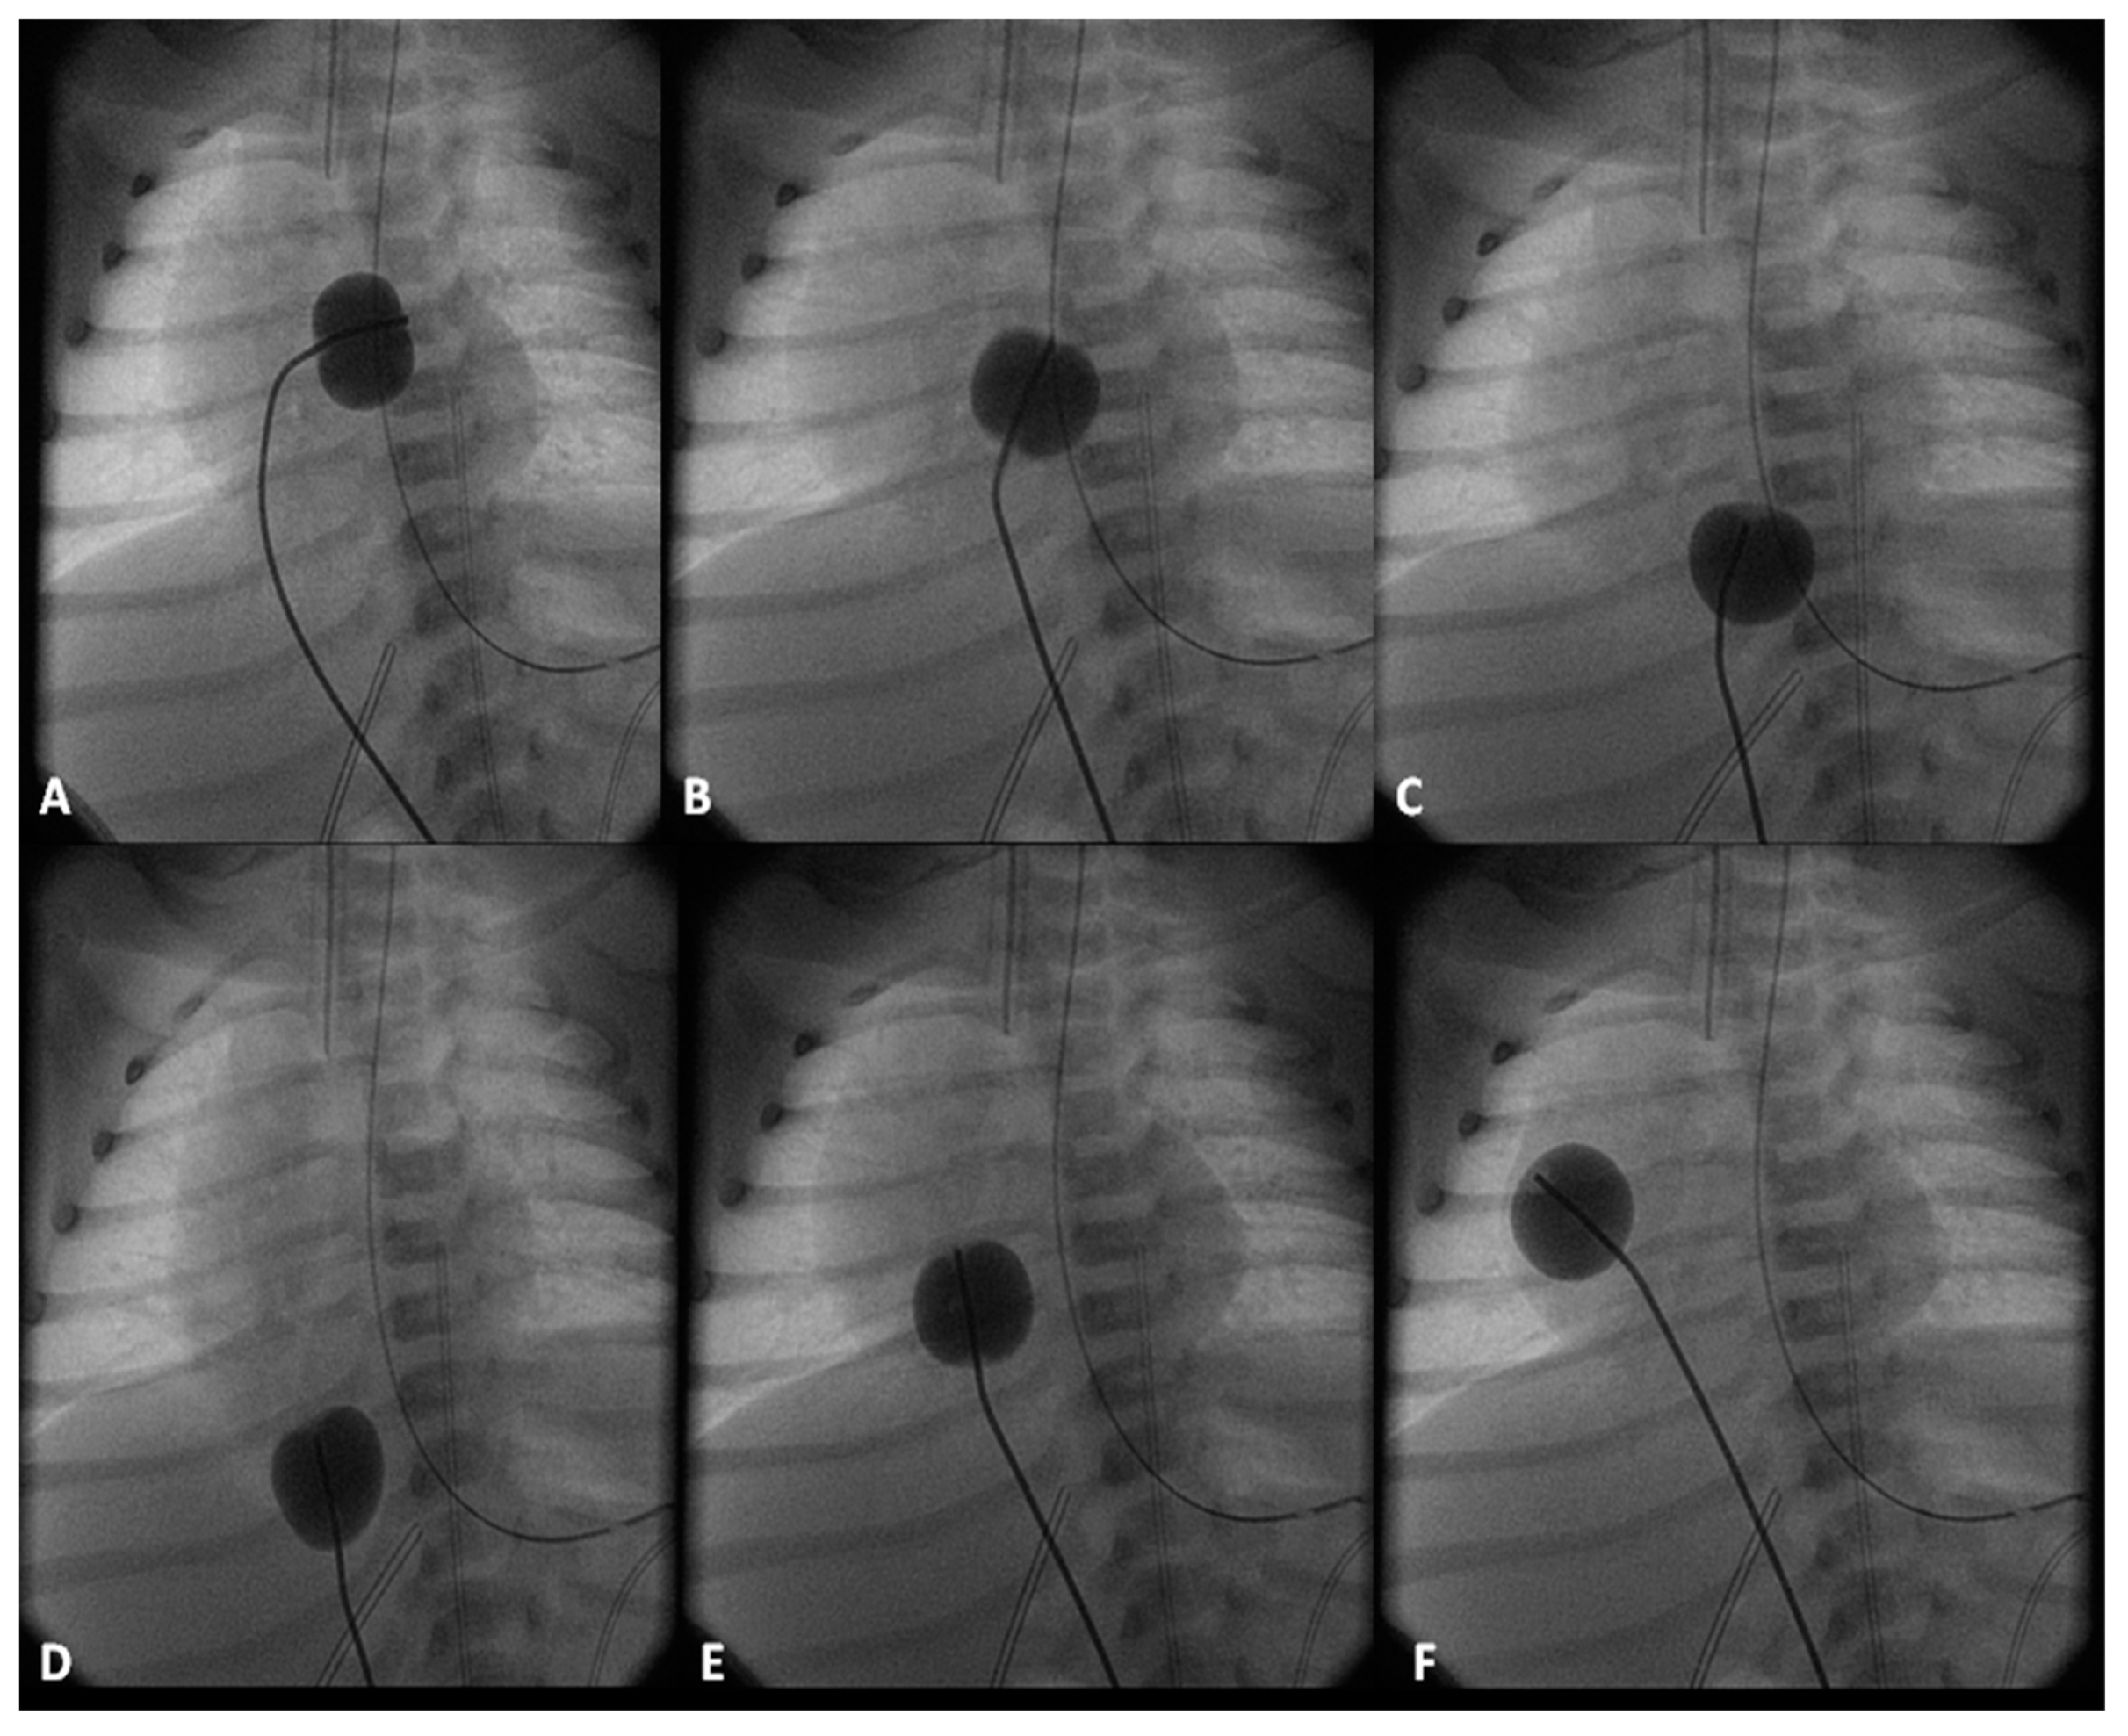

4.2.3. Stage IIIA

Between the ages of one and four years, usually one year after the bidirectional Glenn, Fontan completion is performed by redirecting the inferior vena caval flow into the PA by either a lateral tunnel [81] or an extra-cardiac non-valved conduit [76]. Extra-cardiac conduit with fenestration (Figure 10) is preferred by most surgeons. Cardiac catheterization and selective cine-angiography is usually performed prior to this surgery to evaluate pulmonary artery anatomy and pressures, trans-pulmonary gradient, pulmonary vascular resistance (PVR), and LV end-diastolic pressure to ensure their normalcy prior to proceeding with Fontan completion. Some centers use magnetic resonance imaging (MRI) for evaluation instead of angiography. During this catheterization, significant collateral vessels, if present, are trans-catheter occluded by most cardiologists.

4.2.4. Stage IIIB

The fenestration is closed by trans-catheter device implantation (Figure 11) six months to one year after stage IIIA. Occlusion of the fenestration is not necessary in all patients, although the author recommends closure to prevent arterial desaturation and paradoxical embolism.